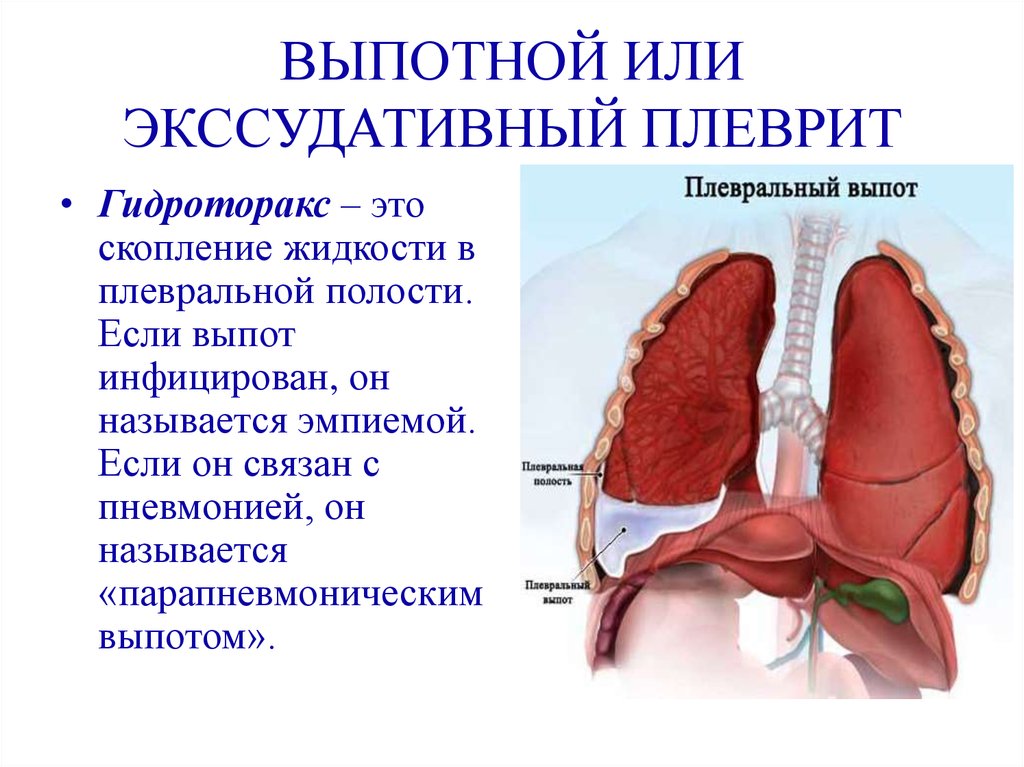

Анатомия межплеврального пространства